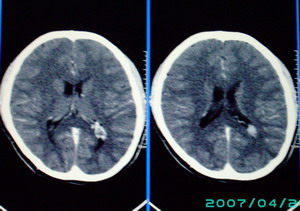

以下是引用九目段在2007-12-24 14:55:00的发言:[br]1,年轻女性[br]2,ct表现:左侧脑室三角区可见一不规则小明显强化的结节,中央见小低密度,侧脑室无扩张。[br]分析:[br]常见的有三种肿瘤好发三角区:[br]1,脉络丛乳头状瘤,好发于年轻者,明显强化,实性,分泌脑脊液,常伴有侧脑室扩大,肿瘤较小可以脑室扩大不明显,不能排除,但小结节尚不易形成坏死腔。[br]2,室管膜瘤,好发于儿童及青少年,明显强化,易坏死,大时伴脑室扩张。[br]3,脑膜瘤,明显强化,圆形,界请,无脑积水,一般不坏死。[br]诊断:[br]左侧脑室三角区结节,考虑室管膜瘤可能性大,不排除脉络丛乳头状瘤和脑膜瘤(因病史较长)。[br][br][本贴已被 九目段 于 2007-12-24 15:13:35 修改过]